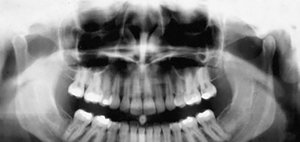

FIG 1 Panoramic view of the TMJ.

Panoramic Radiography: In the past, it was common for these patients to be evaluated utilizing panoramic radiography, typically in the dental office. The panoramic view demonstrates the jaws and the associated structures. This view is helpful in identifying any periodontal or odontogenic causes for orofacial pain. However, this view only demonstrates the lateral part of the condyle due to the superimposition of the zygomatic arch and the base of the skull. (Fig. 1)

Panoramic radiography does not assess the functional status of the TMJ. It only demonstrates late stages of degenerative bone changes, asymmetries of the condyles, fractures and osseous tumors. Panoramic radiography does not demonstrate the functional status of the joint, and has a relatively low specificity and sensitivity when compared with CT, which is more suitable for identifying TMJ changes than conventional radiography.